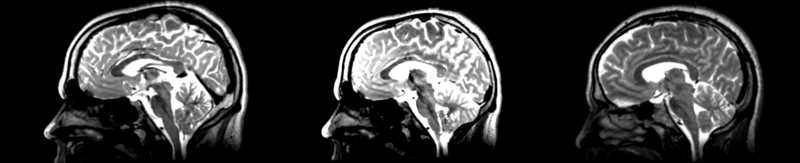

Registration of two different subjects t2 images via the pipe affine selection in the Register Images module.

current20:38, 22 April 2009Thumbnail for version as of 20:38, 22 April 20092,100 × 427 (487 KB)Rauscha (talk | contribs)Registration of two different subjects t2 images via the pipe affine selection in the Register Images module.